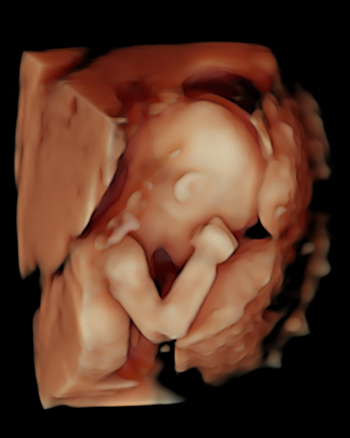

Nossas imagens

Veja algumas de nossas imagens